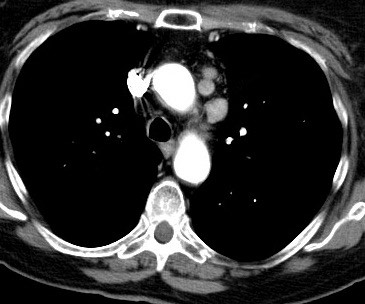

2343. С целью верификации увеличенных медиастинальных лимфоузлов, локализация которых представлена на контраст-усиленном томографическом срезе

у пациентки, перенесшей радикальную резекцию молочной железы по поводу рака и адъювантную лучевую терапию на область средостения, целесообразно использование __________ доступа